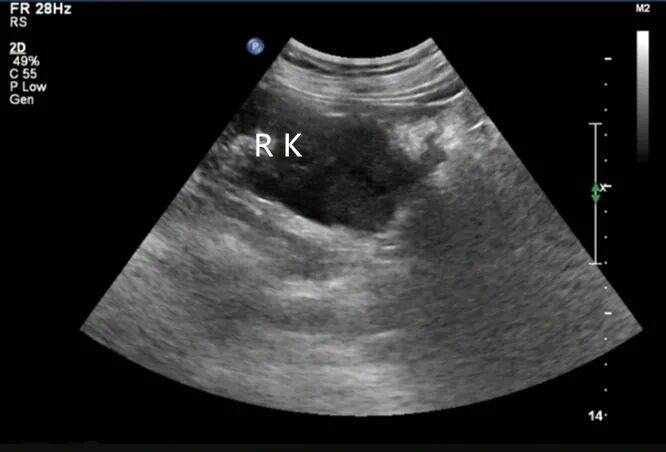

2. 左肾静脉增宽,前后径约 16 mm,其内充满低回声,下腔静脉增宽,前后径约 29 mm,其内充满低回声,向上延伸至右心房入口处。CDFI:左肾静脉、下腔静脉及其内低回声见星点状血流信号(图 3、4)。

图 4 彩色多普勒超声示低回声内见星点状血流信号( RK 右肾 IVC 下腔静脉 L RV 左肾静脉 L RA 左肾动脉 AAO 腹主动脉)